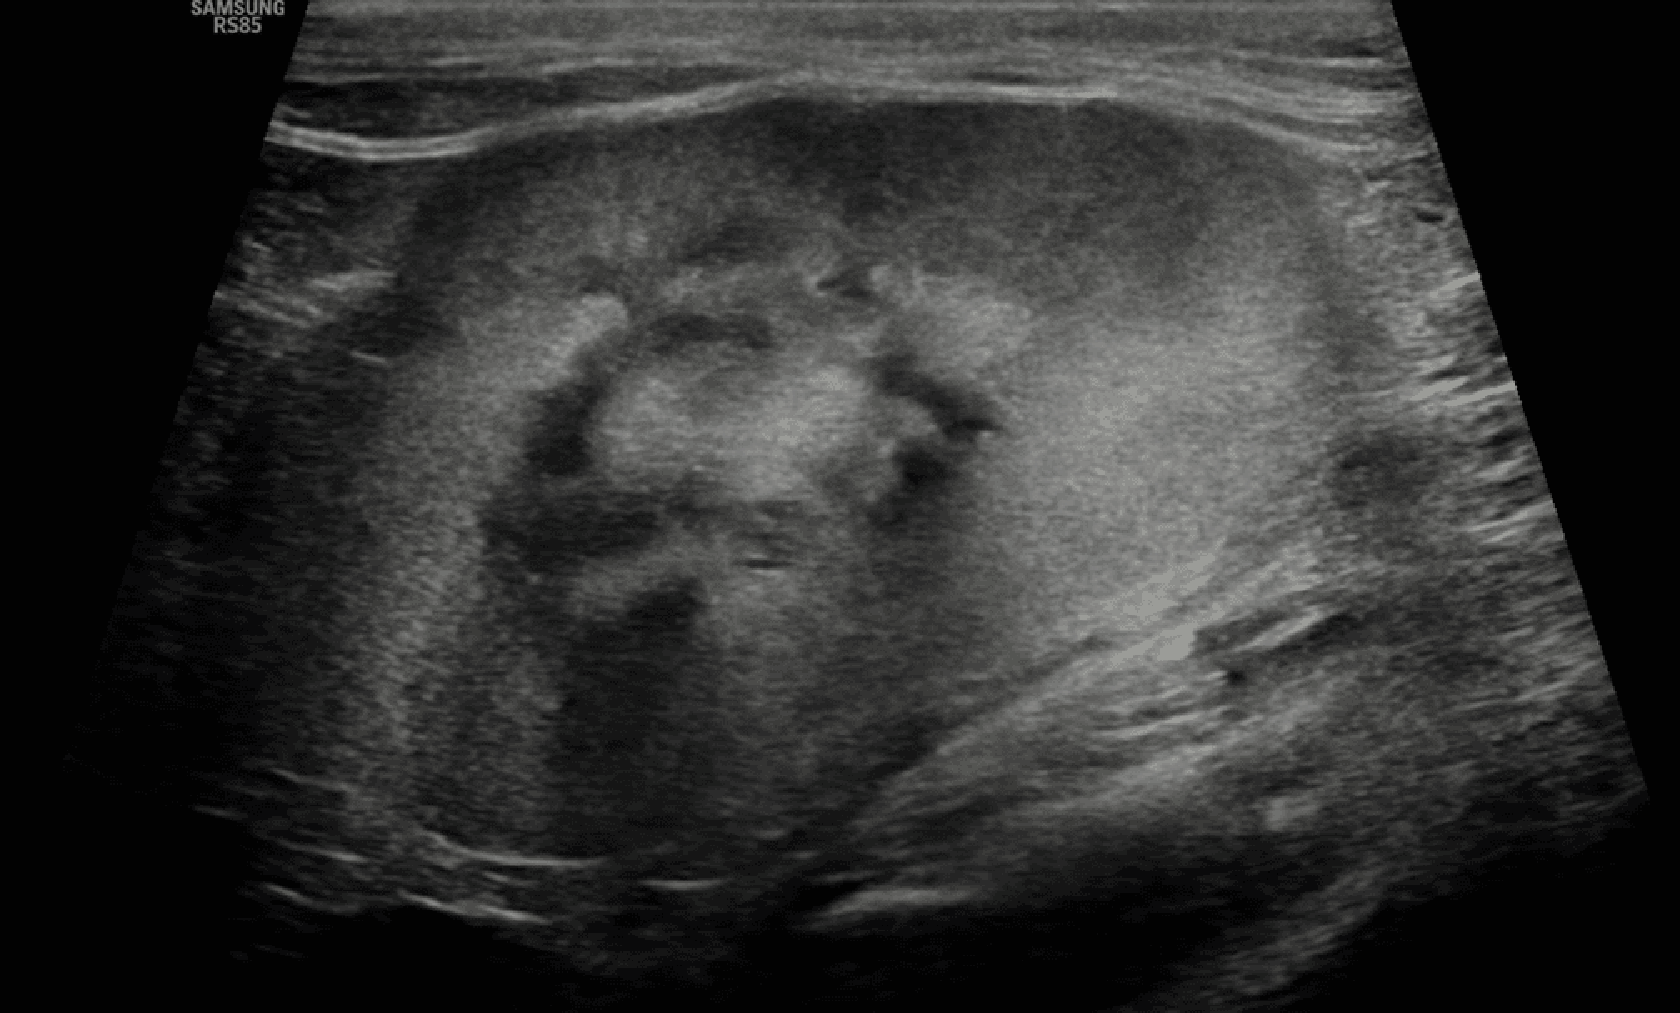

Zmniejszone zróżnicowanie korowo-rdzeniowe

Wyraźne zróżnicowanie między korą a rdzeniem nerki wynika z wyższej gęstości komórkowej w korze oraz większej zawartości płynów w rdzeniu nerki (ryc. 7).15 Wraz ze zwyrodnieniem i utratą zdolności zatrzymywania płynów w rdzeniu nerki echogeniczność rdzenia stopniowo wzrasta, co prowadzi do utraty zróżnicowania między korą a rdzeniem.15

Ryc. 7. Obraz w projekcji strzałkowej prawej nerki kota, ukazujący wyraźnie zmniejszone zróżnicowanie korowo-rdzeniowe, a także hiperechogeniczność kory nerki i jej nieregularne brzegi.